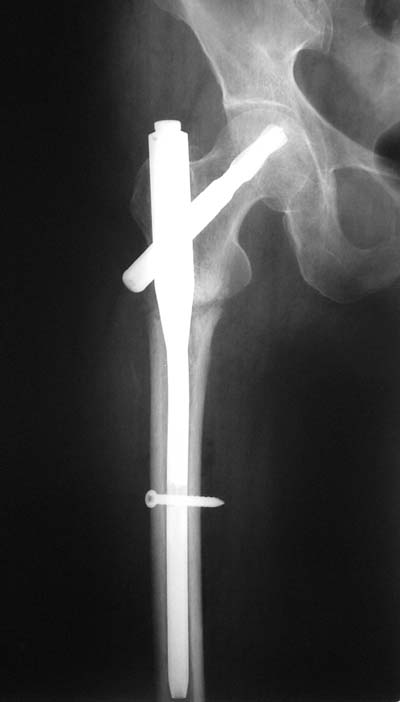

> Здравствуйте коллеги ! Прооперировали женщину 72 лет с Диагнозом: Чрезвертельный перелом

> левого бедра. Первый раз поставили PFN A (SYNTHES) см R-gr.

Дистальное блокирование провели правильно: статическое. Динамическое показано в редких случаях при поперечных подвертельных переломах.

При чрезвертельных переломах динамическая нагрузка на перелом обусловлена конструкцией клинка у PFNa, или винта у Gamma.

И по фасу - шеечый винт можно бы и подлиннее.

Нижний винт тут, насколько я понимаю, не особо нужен, поскольку проксимальный винт проходит через дистальный отломок.